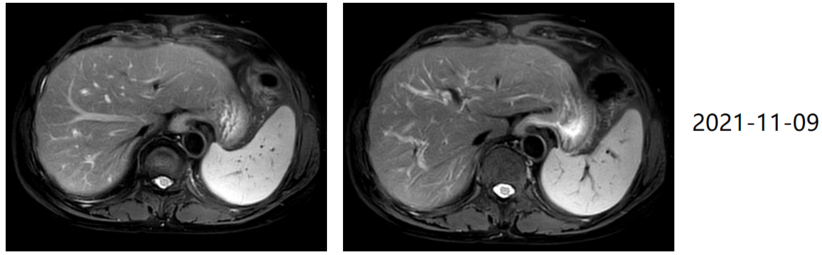

随着临床证据的累积,针对HER2阴性患者,化疗联合免疫治疗已成为一线治疗的标准方案;针对HER2阳性患者,可选择靶向治疗联合化疗+免疫治疗。比如本人经治的一例HER2阳性、PD-L1 CPS=1的晚期胃癌(T3N3M1,IV期,伴肝及多处淋巴结转移)患者,自2020年1月起接受替雷利珠单抗+曲妥珠单抗+化疗一线治疗,2周期后即达部分缓解(PR),6周期后逐步减量进入维持阶段——替雷利珠单抗联合曲妥珠单抗治疗26周期,曲妥珠单抗单药维持16周期。2021年11月评效达完全缓解(CR),直至2025年3月最近一次复查,仍处于CR状态。整体疗程耐受良好,提示替雷利珠单抗联合曲妥珠单抗及化疗方案在HER2阳性、PD-L1 CPS≥1的晚期胃癌中可实现持久缓解与长期生存。